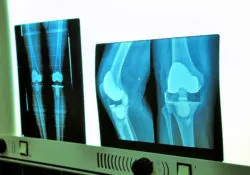

High Viscosity Bone Cement Linked to Premature Knee Implant FailurePatients who have undergone knee replacement surgery are reporting cases of implant failure due to failure of the bone cement used to fix the implants in place.

Not all knee replacement systems require cement. Some types of knee replacement systems rely on the bone growing in and around the implant. In other types of implants, bone cement anchors the implant components to the tibia and the femur.

Even though an X-ray showed the knee replacement system was in a good position, a bone scan revealed loosening of the tibial component. As a result, she underwent a total knee revision surgery in May 2012.